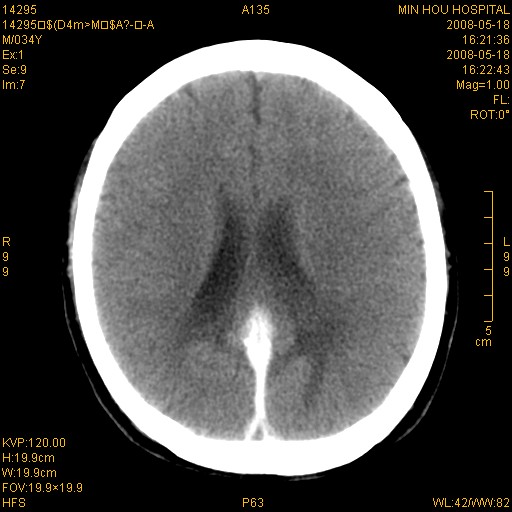

标题: CT13617:双顶叶白质水肿伴大脑镰小脑幕广泛钙化 [打印本页]

标题: CT13617:双顶叶白质水肿伴大脑镰小脑幕广泛钙化

多年前频发抽搐生活不能自理,行ct平扫,诊断为双顶叶占位。因贫未能进一步检查。

目前偶有抽搐,能从事油漆工作。原片未能获取。

双侧侧脑室后脚旁对称性低密度影,符合肾上腺白质营养不良(成人型)改变    小脑幕及大脑廉钙化  可考虑为生理性

支持:1、肾上腺白质营养不良.2、小脑幕、大脑镰广泛钙化。3、建议进一步检查。

硬脑膜钙化是主因,双侧顶叶白质密度减低是可能由于静脉路回流受阻所致。